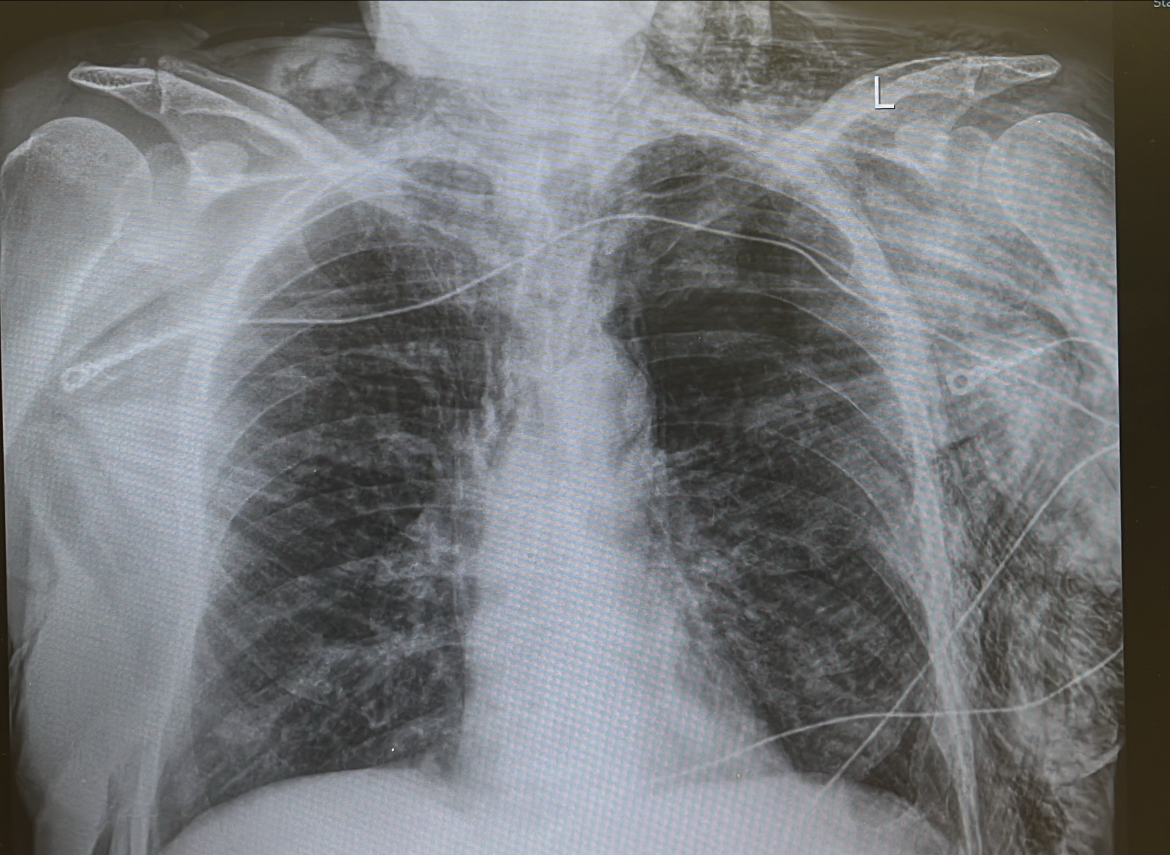

Critical Care Casebook Episode 4: Subcutaneous emphysema

Subcutaneous emphysema is typically benign and resolves on its own without the need for targeted therapy.

In rare instances, it can become extensive enough to threaten the airway. In these situations, small skin incisions (“blowholes”) may be created to facilitate the release of trapped air.

Management should also address the underlying pneumothorax, which generally requires placement of a new chest tube. When subcutaneous emphysema is severe, inserting a pigtail catheter may be technically challenging, and a traditional surgical chest tube may be more appropriate.

If there is concern for impending airway compromise, early intubation should be considered to secure and protect the airway. The use of a “blowhole” technique should be reserved as a last-resort intervention. The blowhole—an incision near the clavicle to release trapped air—is a temporary, last-resort maneuver described mainly in case reports. Definitive management means fixing the underlying lung or tracheal injury.